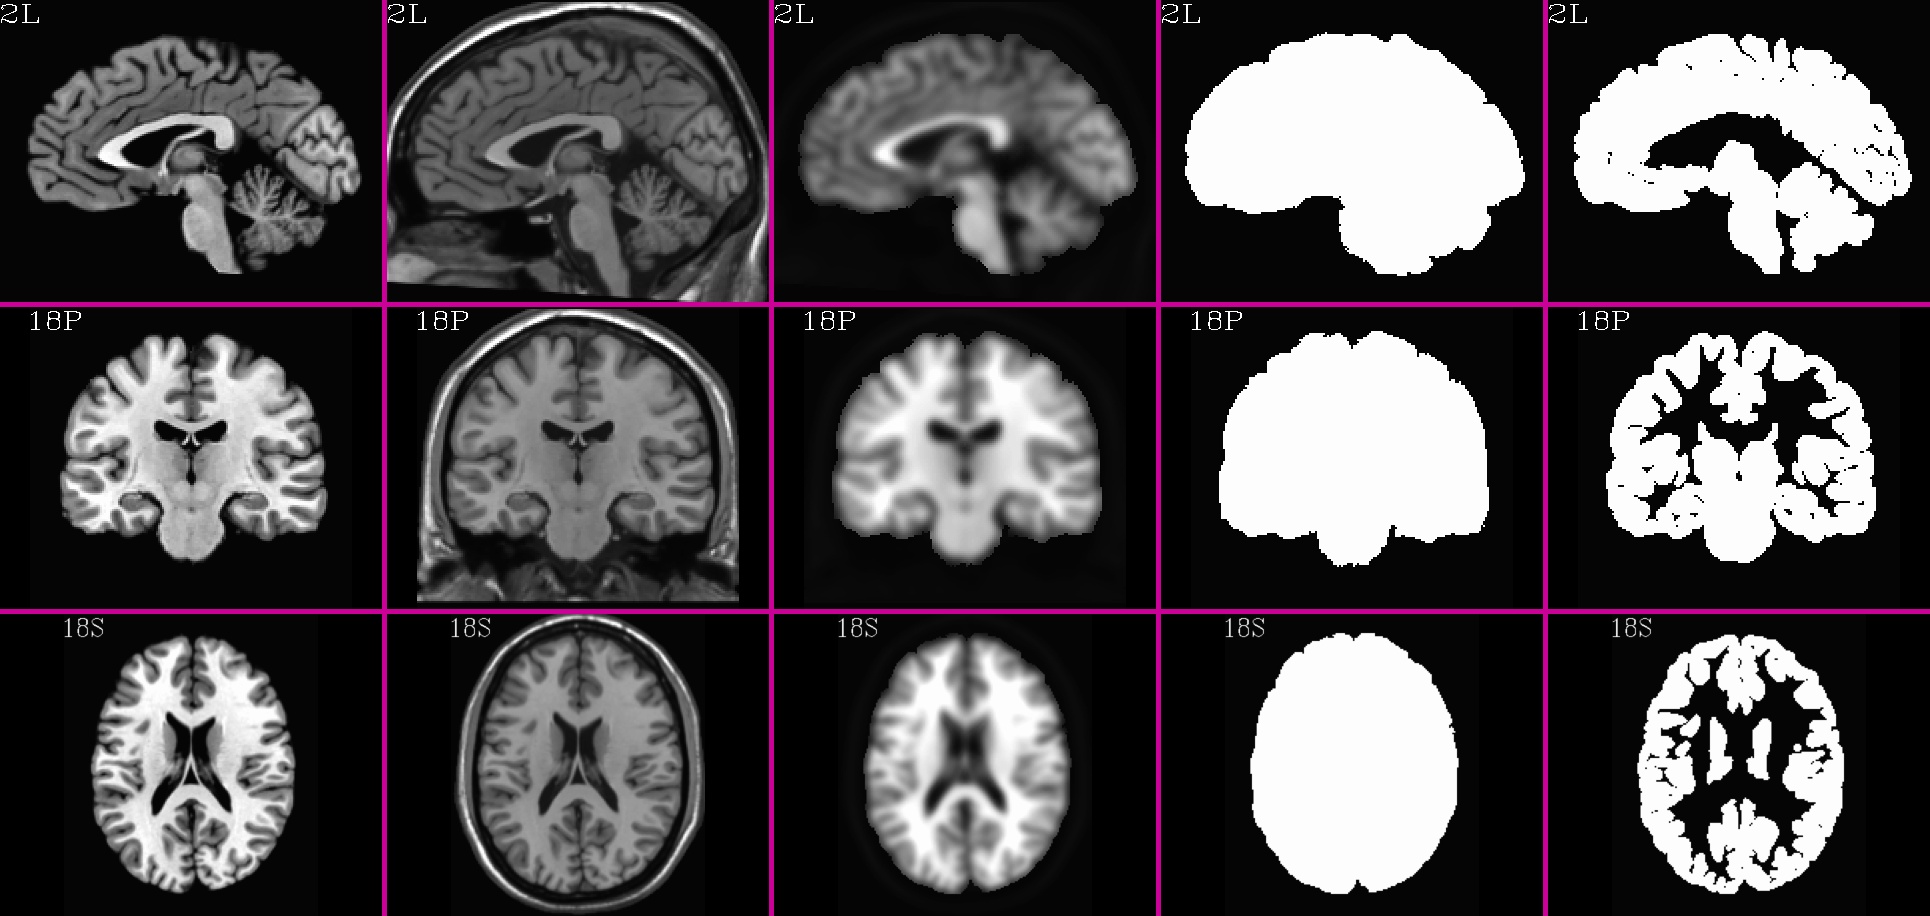

specially-created, multi-volume dataset as a reference. It has five

volumes to it, and (reading from the program’s help), these are:

[0] = skull-stripped template brain volume

[1] = skull-on template brain volume

[2] = weight mask for nonlinear registration, with the

brain given greater weight than the skull

[3] = binary mask for the brain

[4] = binary mask for gray matter plus some CSF (slightly dilated)

-- this volume is not used in this script

-- it is intended for use in restricting FMRI analyses

to the 'interesting' parts of the brain

-- this mask should be resampled to your EPI spatial

resolution (see program 3dfractionize), and then

combined with a mask from your experiment reflecting

your EPI brain coverage (see program 3dmask_tool).

MNI152_2009_template_SSW.nii.gz (5 volumes; one volume per column; axi, cor, sag views) |

HaskinsPeds_NL_template1.0_SSW.nii.gz (5 volumes; one volume per column; axi, cor, sag views) |